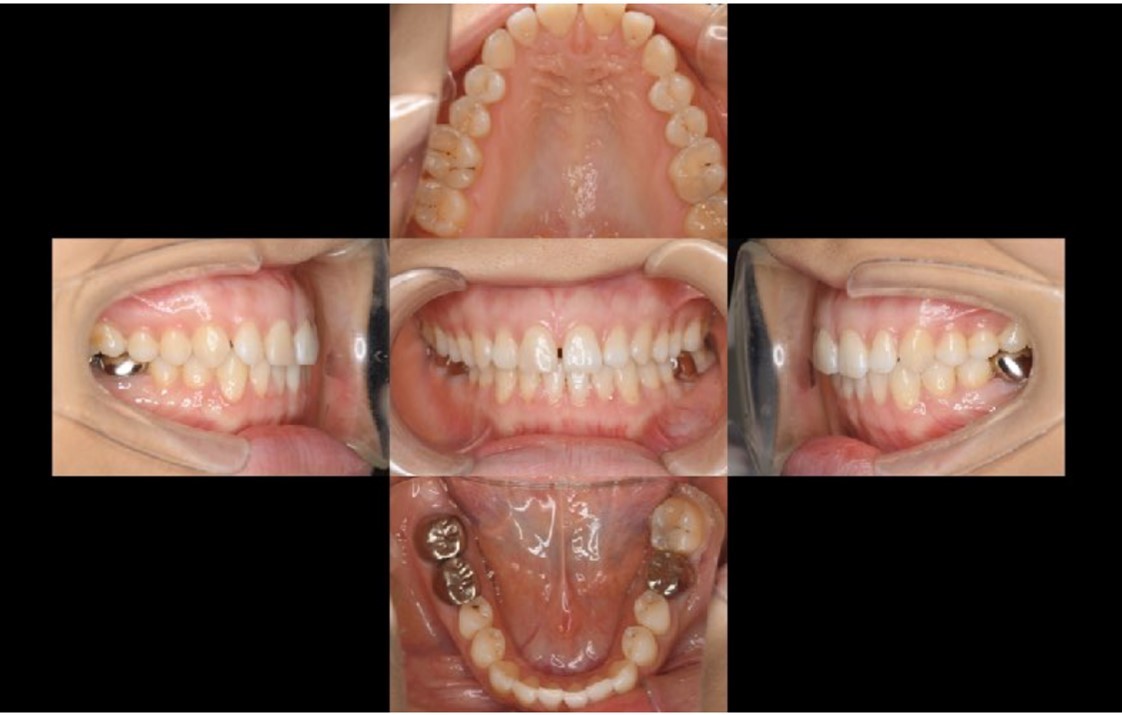

A 27-year-old female patient came to us with discomfort in the right lower jaw (Figure 1). Her primary symptoms were pain in the lower right tooth when biting and discomfort associated with not being able to chew well with the lower left single denture. The patient was married and had one young child, and previously received dental treatment in China, then had returned to Japan for childbirth and early childcare. The patient was a nonsmoker with moderate plaque control and medical history taking revealed no problems. In clinical and radiographic examinations, a root fracture was observed on tooth #46, which had been endodontic ally treated and restored with a full-cast metal crown. Periodontal probing revealed a pocket depth of 8 mm on the buccal center side of the tooth. No pain was detected with percussion and mobility of the tooth was normal. (Figure 1, Figure 2, Figure 3).

For this case, a bridge, partial denture, implant, and auto transplantation were each considered to be possible options, with the advantages and disadvantages of each explained to the patient. Her stated desire was for inexpensive treatment, preservation of adjacent teeth, and no denture, because she was not chewing well on the lower left side. In contrast to a bridge, a denture has the advantage of both adjacent teeth not being cut, while advantages of a bridge are that it is fixed and provides improved functionality. Also, in contrast to an implant, it is less expensive. After explaining these points and discussion with the patient, we decided to perform autotransplantation. Panoramic photograph findings showed that #48 had a complete root tooth with stage 7 growth 17, according to the Moorrees classification 18. Informed written consent was obtained from the patient prior to the procedure and treatments were performed according to the Declaration of Helsinki.

Following the operation, root canal treatment was performed as noted above. Functions including temporary crown occlusal contact and tooth mobility, as well as pocket depth were also checked. All examination results clearly indicated placement of a definitive prosthesis in the patient (Figure 13, Figure 14). At a follow-up examination one year after surgery, progress in this case was determined to be good (Figure 15).

The patient actively visited the clinic for maintenance and showed good compliance. Achievement of occlusal recovery using auto transplantation for prosthetic treatment of the missing right and left mandibular first molars fulfilled her wishes, and created a significant improvement in functionality, thus leading to improved quality of life.